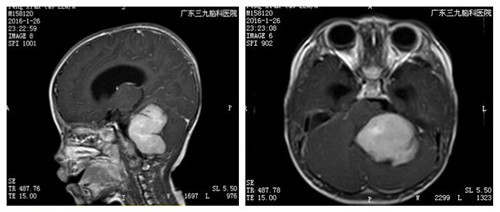

2016年1月,刚满1岁的滔滔突发头痛、呕吐,而且有走路不稳的症状。在当地一家医院以“胃病”治疗一段时间后,病情不但没有好转,反而愈发严重。后查头颅CT,显示:左侧小脑占位性病变,梗阻性脑积水。于是,父母带他来到广东三九脑科医院就诊,经小儿神经外科杨宝应主任面诊,考虑滔滔患髓母细胞瘤的可能性大。

▲术前